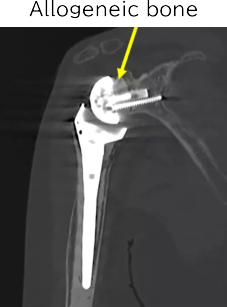

Coronal CT

A deeply concave glenoid

CT scan six years after surgery